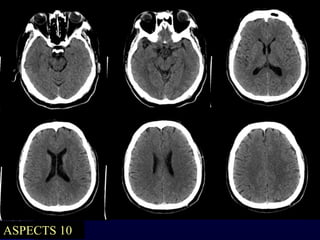

Case 2 – Mr. RD

NCCT

 L eye deviation, L HMCA

 ASPECTS 10

CTA not done…

 Obvious HMCA

 Disabling NIHSS

 Avoid delays to Angio (NCCT already done)

ASPECTS 10